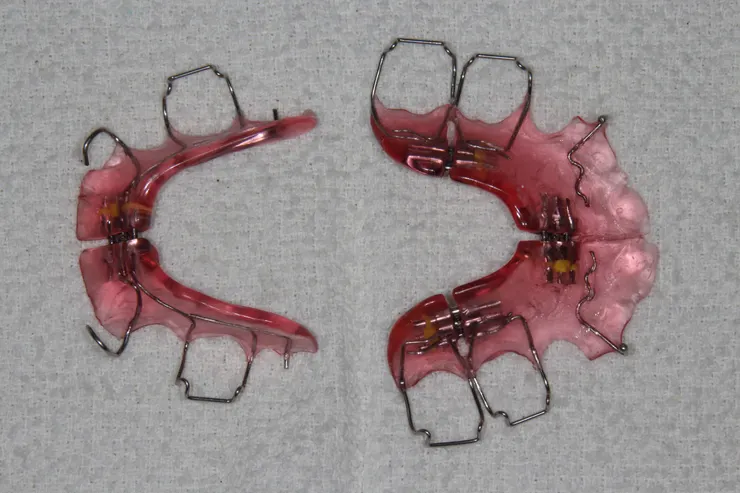

• 擴大板(是重點,不要忘了照,正反面都要照,有時會反光看不清楚,可以多照幾張)

• MRC、EF、PreOrtho、蛙嘴等彈性裝置(裝置不用照),除了口內照,再請加以下這兩張

每種功能性矯正裝置所咬拍攝的點,不一樣喔 口內照是共通點,都要照的 擴大板(是重點,不要忘了照,正反面都要照,有時會反光看不清楚,可以多照幾張) MRC、EF、PreOrtho等彈性裝置(裝置不用照),除了口內照,再請加以下這兩張 反向面弓(如有,請加拍正/側面,有戴裝置2張,沒有時(素顏)2張)